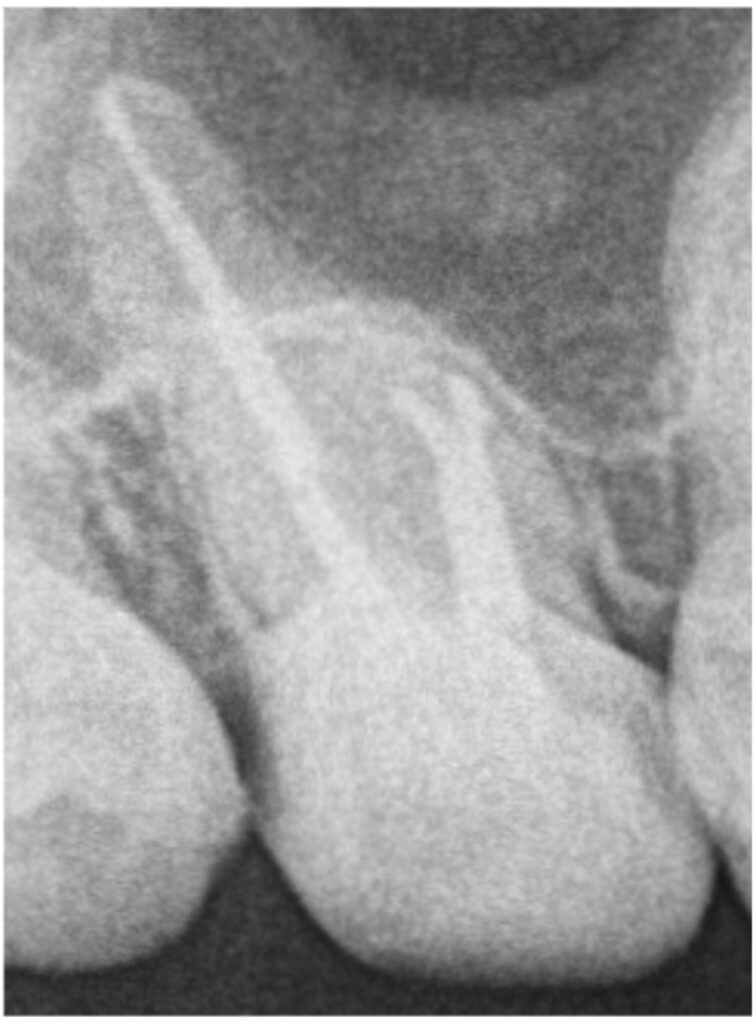

治療前にはっきりと写っていた根の先の材料ですが、術後12ヶ月では完全に消失しています。治療前には強く感じていた鈍い痛みもなくなり、良好な状態を維持しています。

根管治療は、マイクロスコープが無い場合や、適切な手技が行われていない場合、本症例のようにパーフォレーションという歯の根の中に穴があく問題が起こり得ます。また、そこから材料が根の外に飛び出している場合、除去は困難です。しかし、“治らないのは飛び出た材料が原因か?”というと、決してそうとは言い切れません。根管内の細菌を減少させ、外部から細菌感染しないよう封鎖することで、本症例のように治癒に至る可能性は十分にあります。

今回の患者様の場合、飛び出た材料は治癒とともに自然と消失しました。(おそらく)吸収性の材料ではありませんが、身体の自己免疫機構が働き、異物として貪食され消失したと推測されます。多くの場合、根尖孔外の異物は残存したままで治癒します。そのため、今回のように綺麗に消失することは比較的稀であるといえるでしょう。また、もしも根尖孔外に飛び出た材料が原因で治癒しない場合には、外科的歯内療法の適応となります。